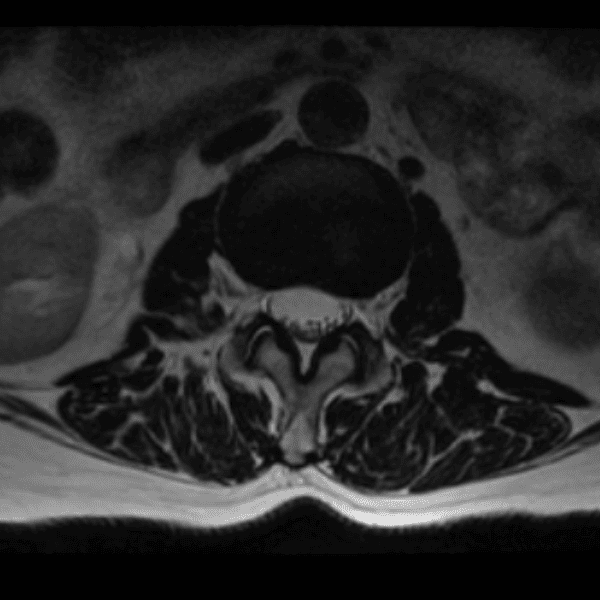

Simulates call by including subtle or difficult cases and some normals.

35 cases